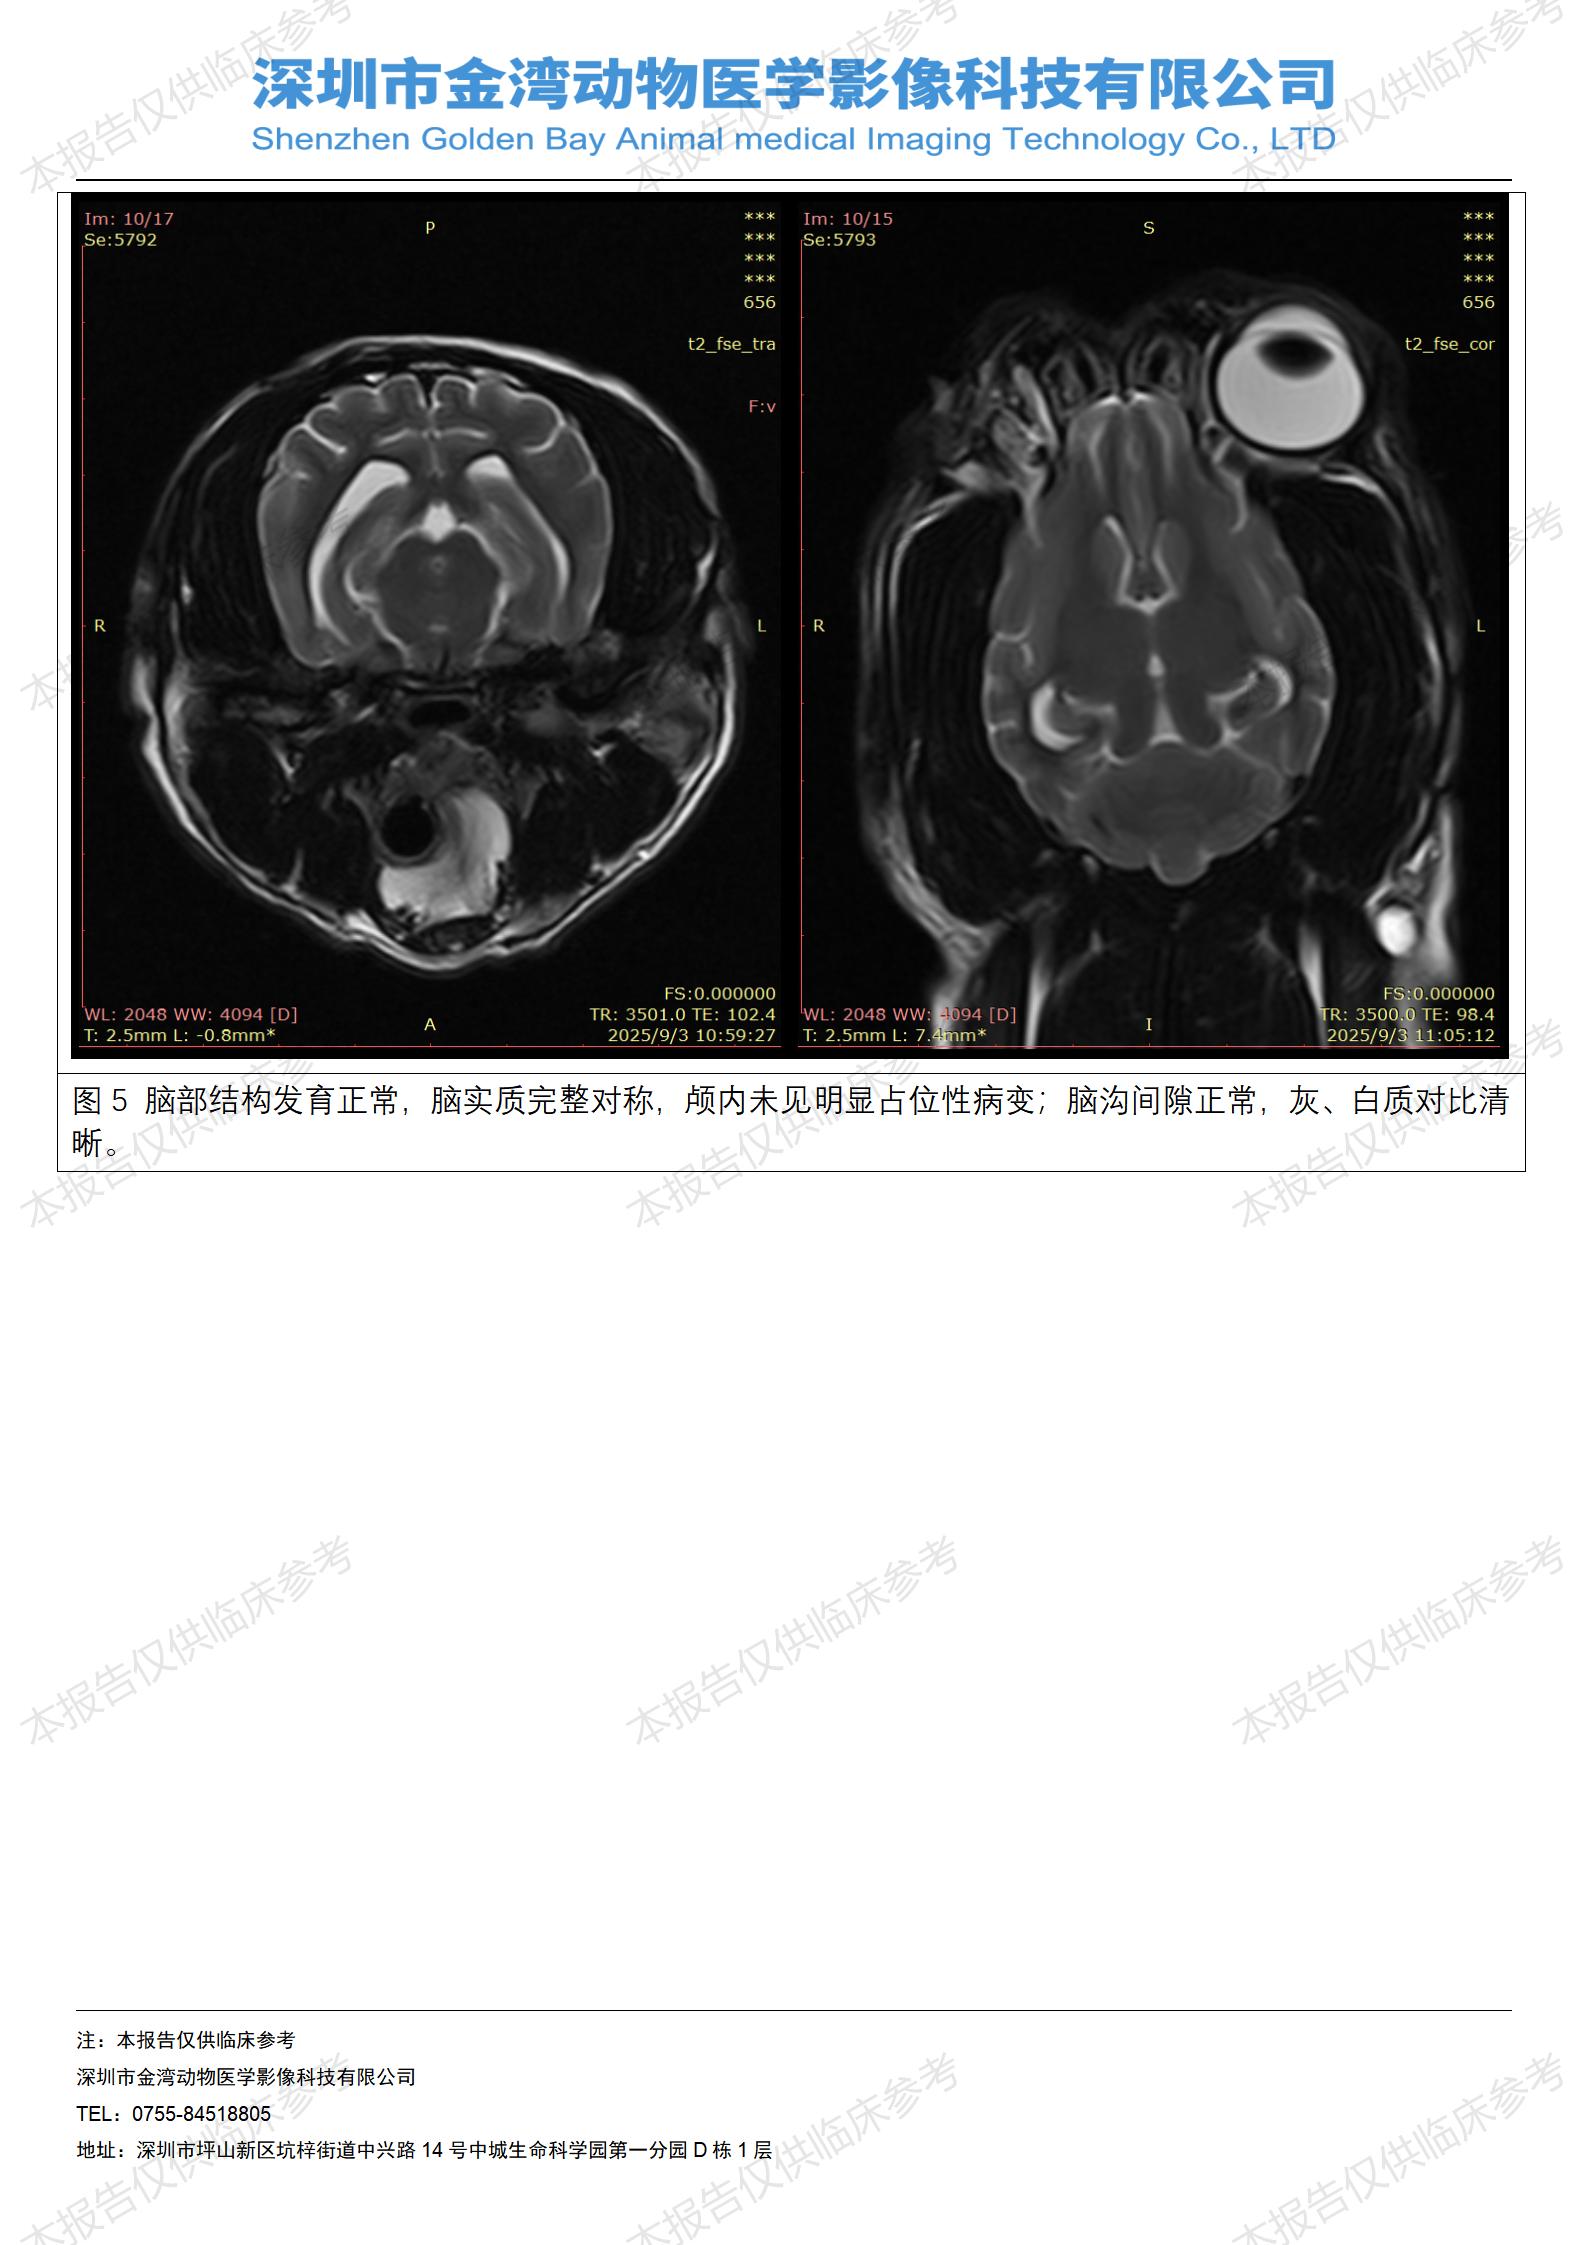

金石医疗MRI影像诊断案例:一例狗双耳流脓的诊断报告